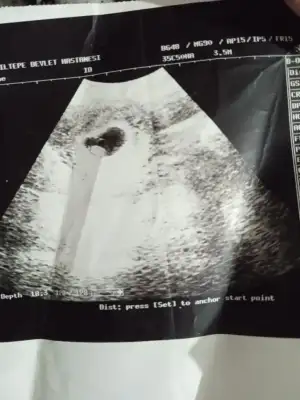

Cinsiyet tahmini

Erkek gibi

6-7 haftalık olması lazımMerhaba..5haftalik tahmin eder misiniz

Canım nubu görünmemiş başka yok mubende tahmin ala bilirmiyim 11+5 vaginal.

Malesef… neyse 10 beklemek zorundayim artik ozaman kesin olarak söyler doktorumCanım nubu görünmemiş başka yok mu

Sanki kizMerhabalar tahmin alabilirmiyim kızlar12 haftalık

Bana da yorum yaparmışsınız 11+4.

Bana da bakar misinizKiz Bebeknub gözüküyor sanki

Merhaba bana da yorum yapabılır mısınız rıca etsem 2.foto 6+1 günlük karındanRamzi teorisi var.ona gore soyledim ama ne kdr gercekci bilemiyorumsonucta kanitlanmis birsey degil bence